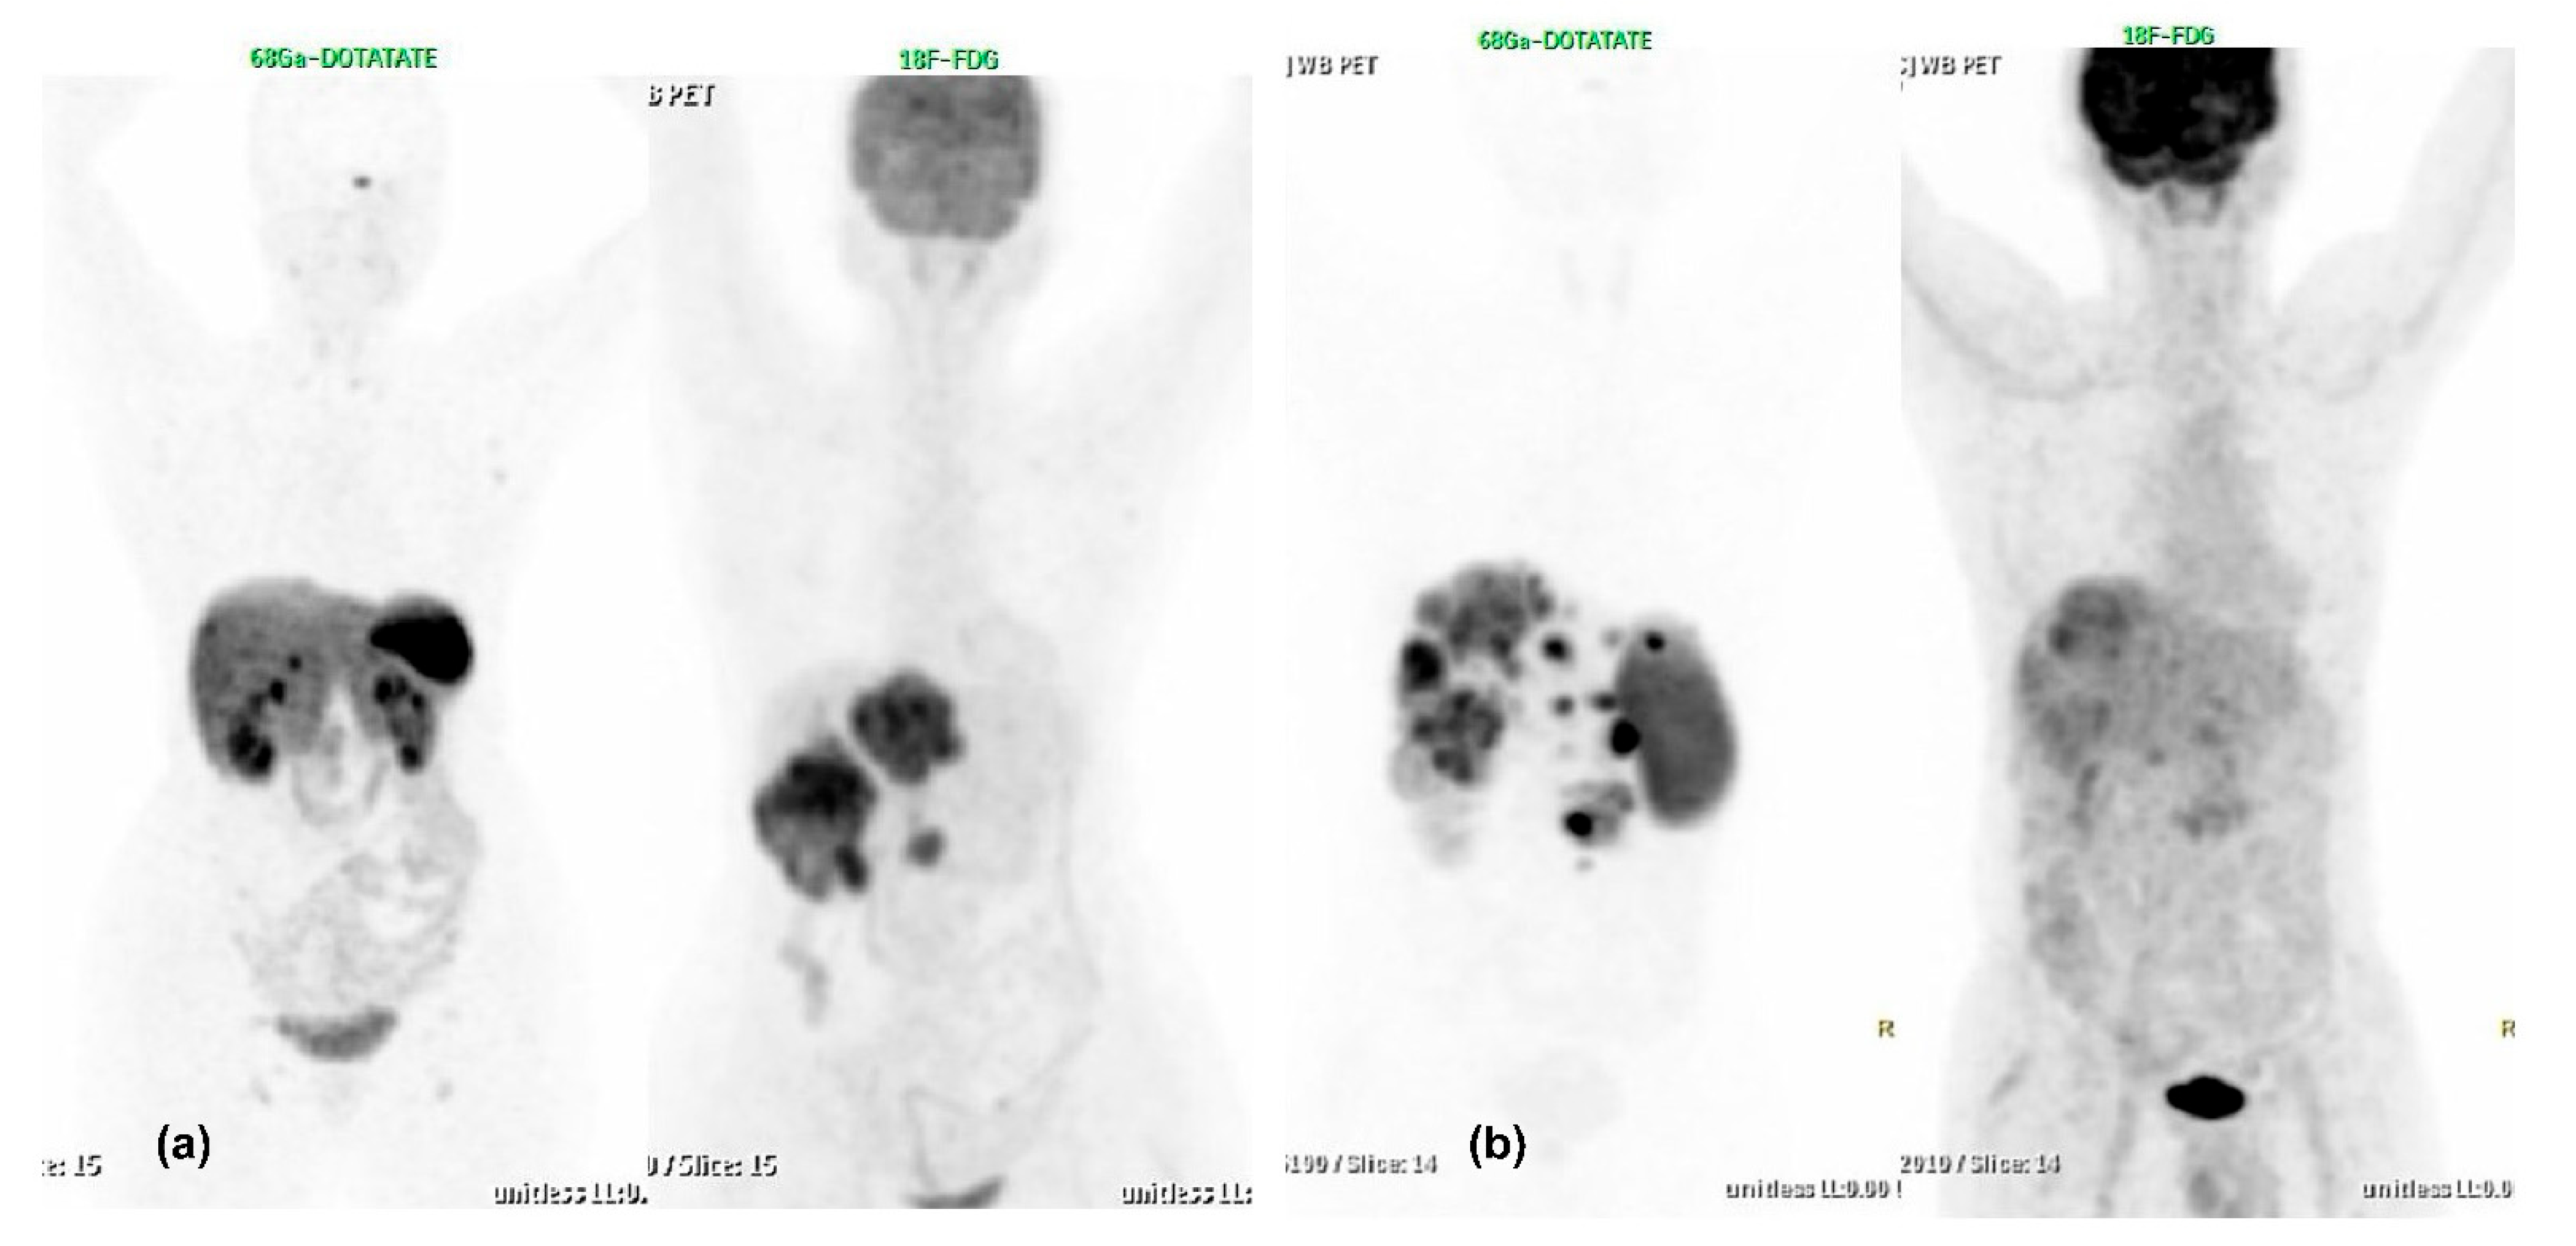

- Chan, D.L.; Pavlakis, N.; Schembri, G.P.; Bernard, E.J.; Hsiao, E.; Hayes, A.; Barnes, T.; Diakos, C.; Khasraw, M.; Samra, J.; et al. Dual Somatostatin Receptor/FDG PET/CT Imaging in Metastatic Neuroendocrine Tumours: Proposal for a Novel Grading Scheme with Prognostic Significance. Theranostics 2017, 7, 1149–1158. [Google Scholar] [CrossRef]

- Karfis, I.; Marin, G.; Levillain, H.; Drisis, S.; Muteganya, R.; Critchi, G.; Taraji-Schiltz, L.; Guix, C.A.; Shaza, L.; Elbachiri, M.; et al. Prognostic value of a three-scale grading system based on combining molecular imaging with 68Ga-DOTATATE and 18F-FDG PET/CT in patients with metastatic gastroenteropancreatic neuroendocrine neoplasias. Oncotarget 2020, 11, 589–599. [Google Scholar] [CrossRef] [PubMed]

- Chan, D.L.; Hayes, A.R.; Karfis, I.; Conner, A.; O’Mahony, L.F.; Mileva, M.; Bernard, E.; Roach, P.; Marin, G.; Pavlakis, N.; et al. Dual [68Ga]DOTATATE and [18F]FDG PET/CT in patients with metastatic gastroentero-pancreatic neuroendocrine neoplasms: A multicentre validation of the NETPET score. Br. J. Cancer 2023, 128, 549–555. [Google Scholar] [CrossRef]

- Adnan, A.; Basu, S. Discordance Between Histopathologic Grading and Dual-Tracer PET/CT Findings in Metastatic NETs and Outcome of 177Lu-DOTATATE PRRT: Does In Vivo Molecular PET Perform Better from the Viewpoint of Prediction of Tumor Biology? J. Nucl. Med. Technol. 2021, 50, 248–255. [Google Scholar] [CrossRef]